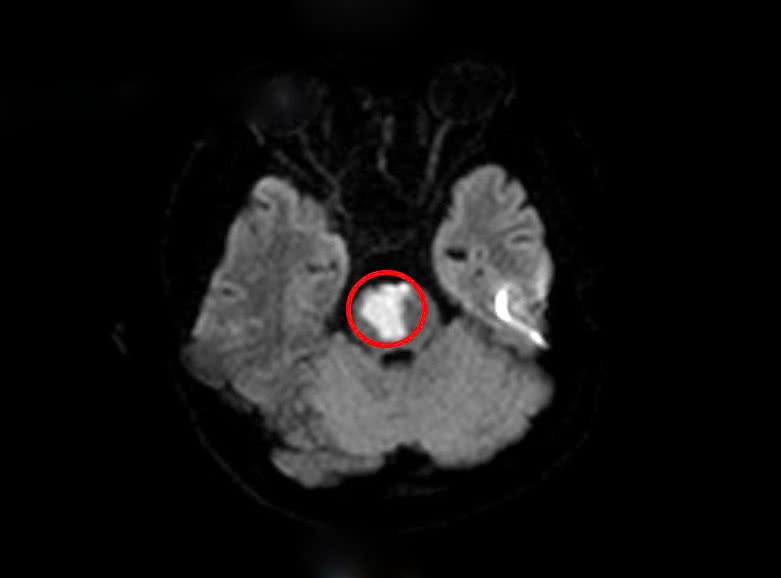

Sau khi khai thác tiền sử, các bác sĩ nghĩ nhiều đến tình trạng đột quỵ não và cho chỉ định tiến hành chụp MRI sọ não. Kết quả cho thấy người bệnh có khối nhồi máu tiểu não, cầu não do tắc động mạch thân nền.

Theo bác sĩ bệnh viện cho biết: trên kết quả xét nghiệm máu có rối loạn lipid máu, một yếu tố nguy cơ dẫn đến các vấn đề tim mạch và mạch máu não. Ngoài ra khi làm các xét nghiệm chuyên sâu, người bệnh được phát hiện bất thường trong hệ gen gây tăng nguy cơ tạo huyết khối tắc mạch.

Trường hợp người bệnh rất trẻ, nhưng lại có bệnh lý giữa nhồi máu tiểu não, cầu não và rối loạn lipid máu đã dẫn đến một tình trạng rất nghiêm trọng. Các bác sĩ đã nhanh chóng thực hiện các biện pháp cấp cứu, hội chẩn cùng Trung tâm đột quỵ Bệnh viện Bạch Mai và có phương pháp điều trị phù hợp cho người bệnh.